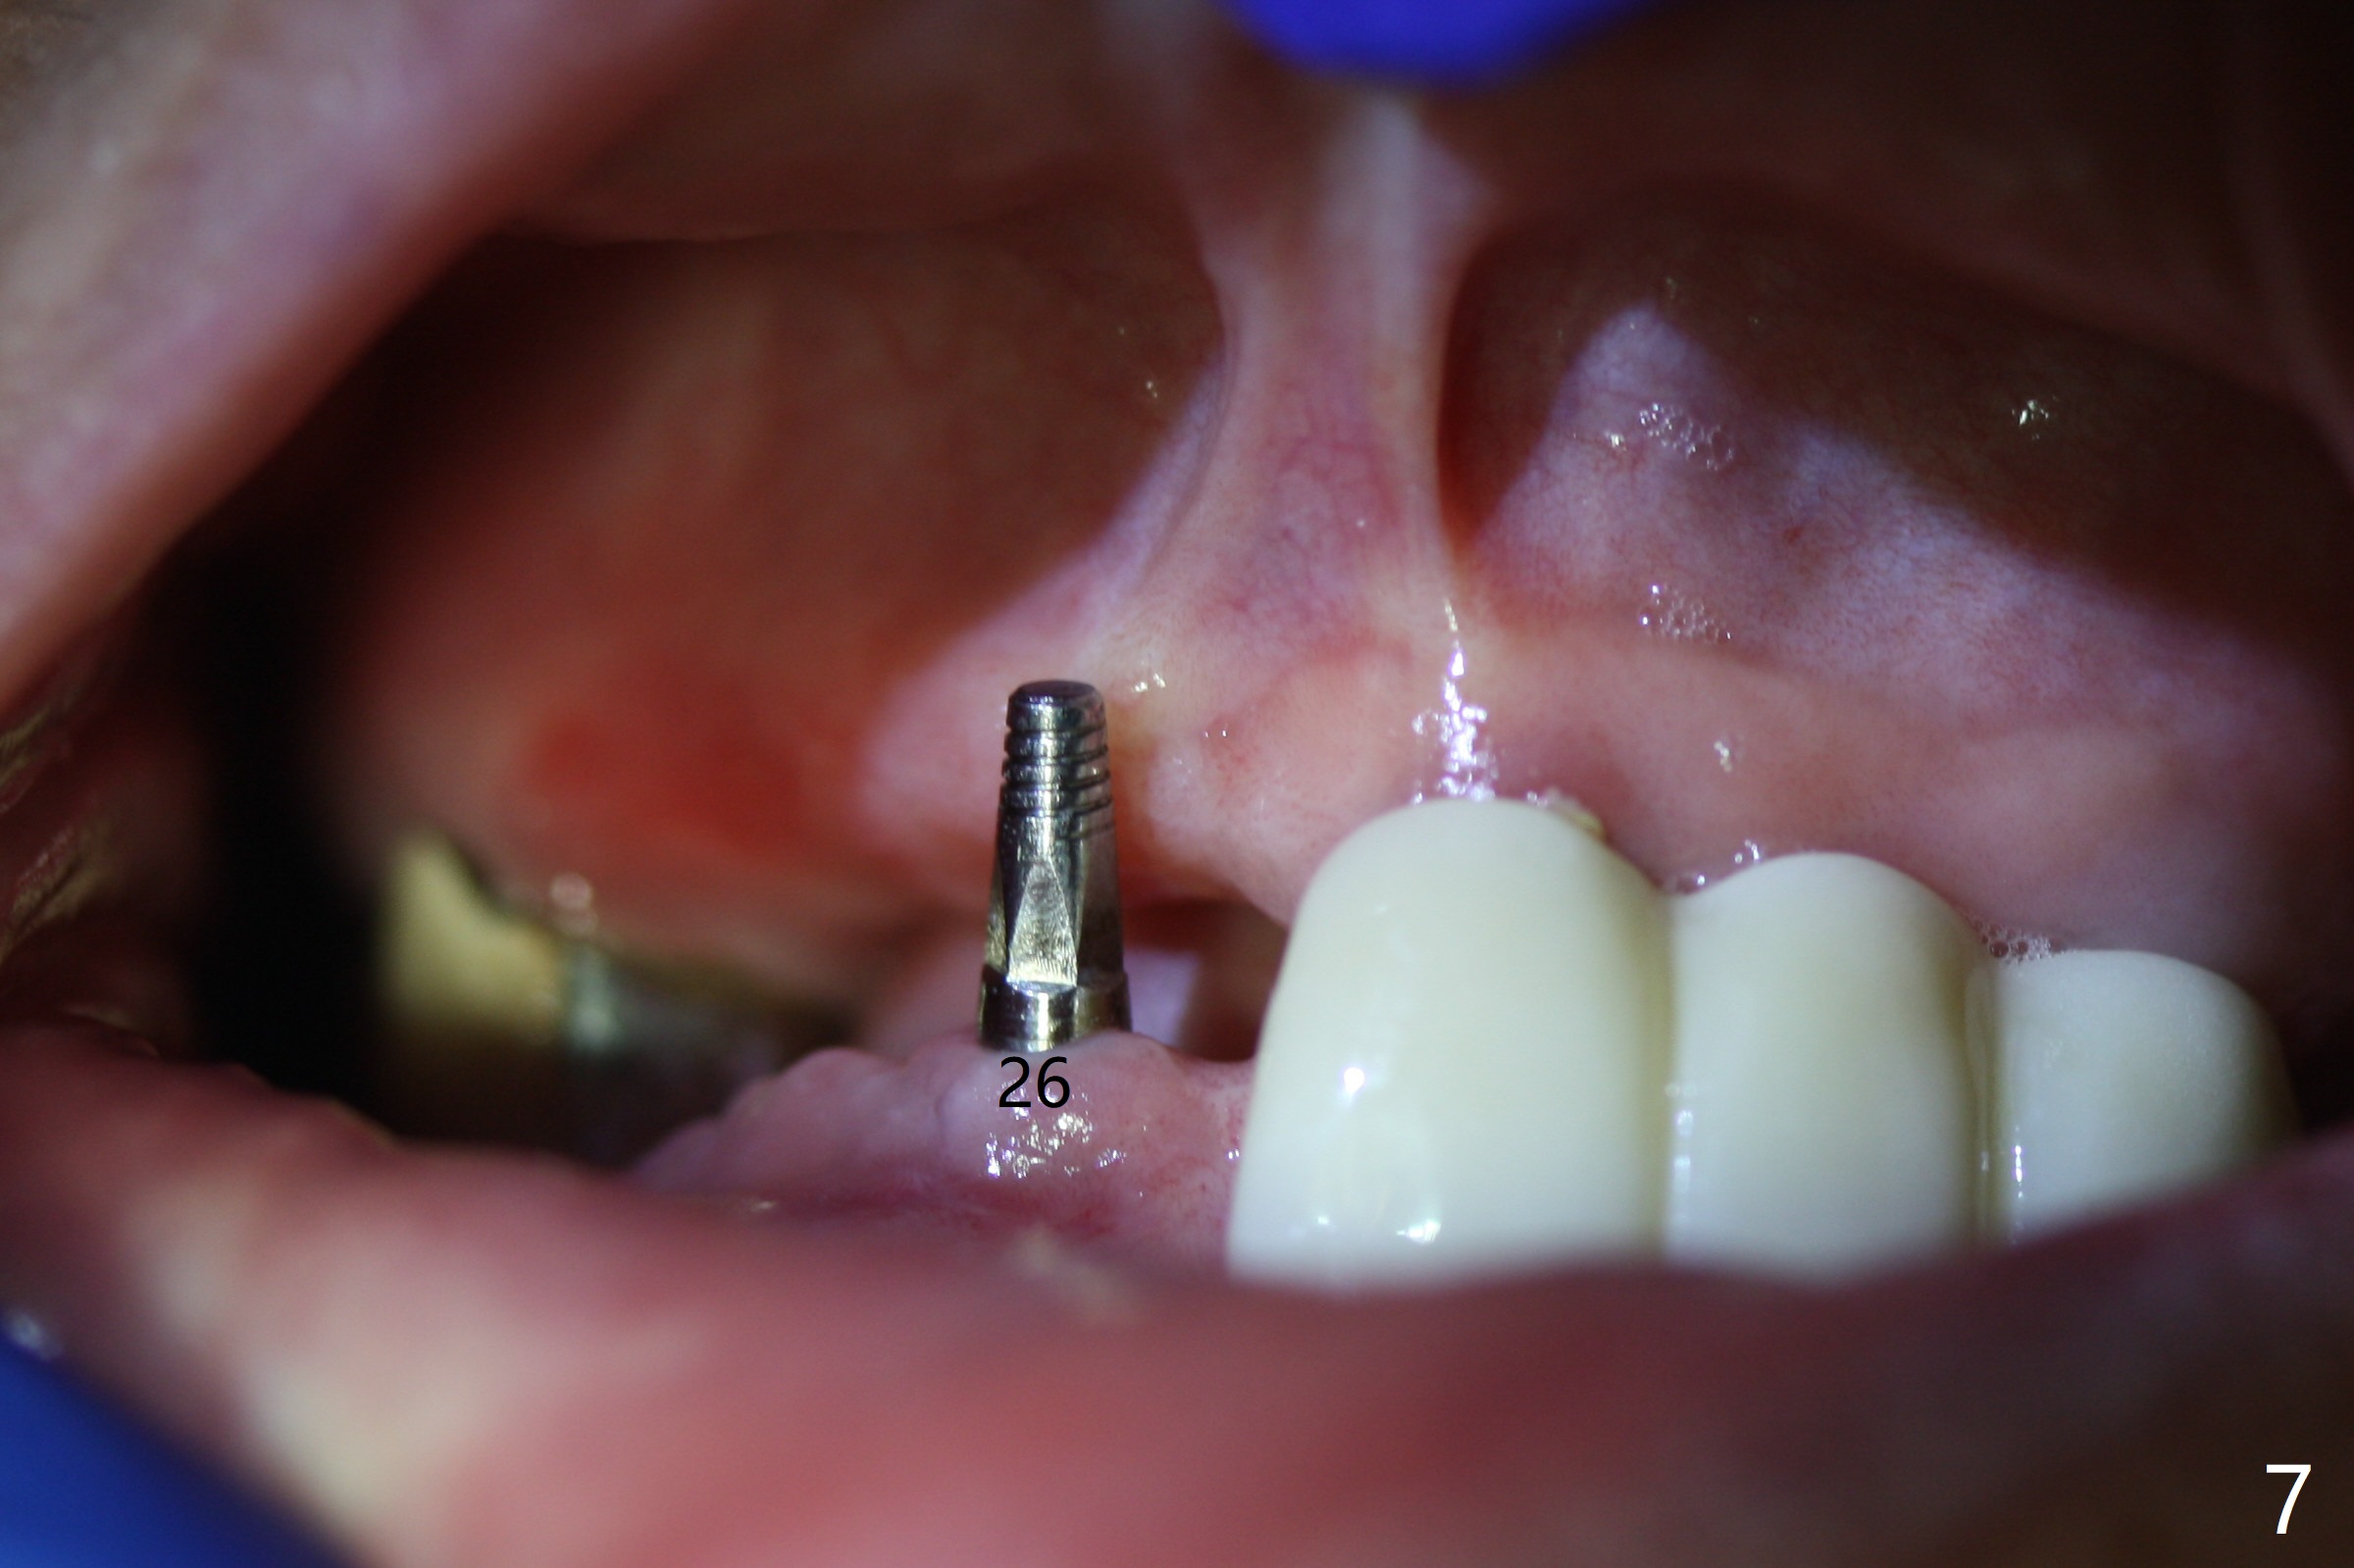

When the patient returns 4 months post #26 implant 2nd placement, the fractured crowns at #20 and 21 are loose. The roots are not difficult to remove. Since the bone height is limited (Fig.1,2), immediate implants are 3.8x8 and 3.8x10 mm, respectively with insertion torque >30 Ncm. Ball abutments (3.9x2 mm) are placed at #20 and 21; the existing lower RPD is soft relined using #26 1-piecee implant as an abutment. The retention of the RPD improves. Another implant will be placed in the lower right quadrant. One month 10 days postop, the ball abutment at #21 seems to be low (Fig.6). It is removed after laser gingivectomy and replaced with a ball abutment with 4 mm cuff. When the patient closes without RPDs, the 1-piece implant at #26 is barely buccal to the upper ridge (Fig.7). It appears that crowns have to be fabricated at #20,21,26 and 27 prior to refabrication of the lower RPD.